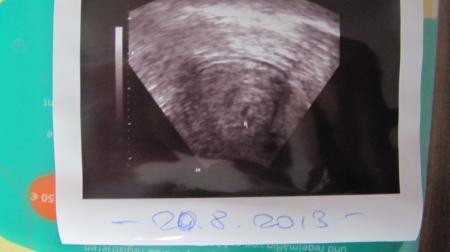

Oh weh, du Arme... da musstest du ja wirklich viel mitmachen, dück dich mal Ich kann deine Sorgen verstehen, ich glaube da könnte niemand von uns hier Weihnachten genießen. Sehr viel helfen kann ich dir nicht aber ich kann dir schildern was man bei meinem HCG-Wert sehen konnte. Mein HCG war bei 4+3 bei 1250 am gleichen Tag wurde dieses Bild der Fruchthöhle gemacht und mir wurde gesagt es wäre alles in bester Ordnung, seh selbst...erklären kann man soetwas meist schlecht. Ich drück Euch die Daumen....vllt. passiert noch ein Weihnachtswunder und am 28.12 ist alles gut.

Bild zu